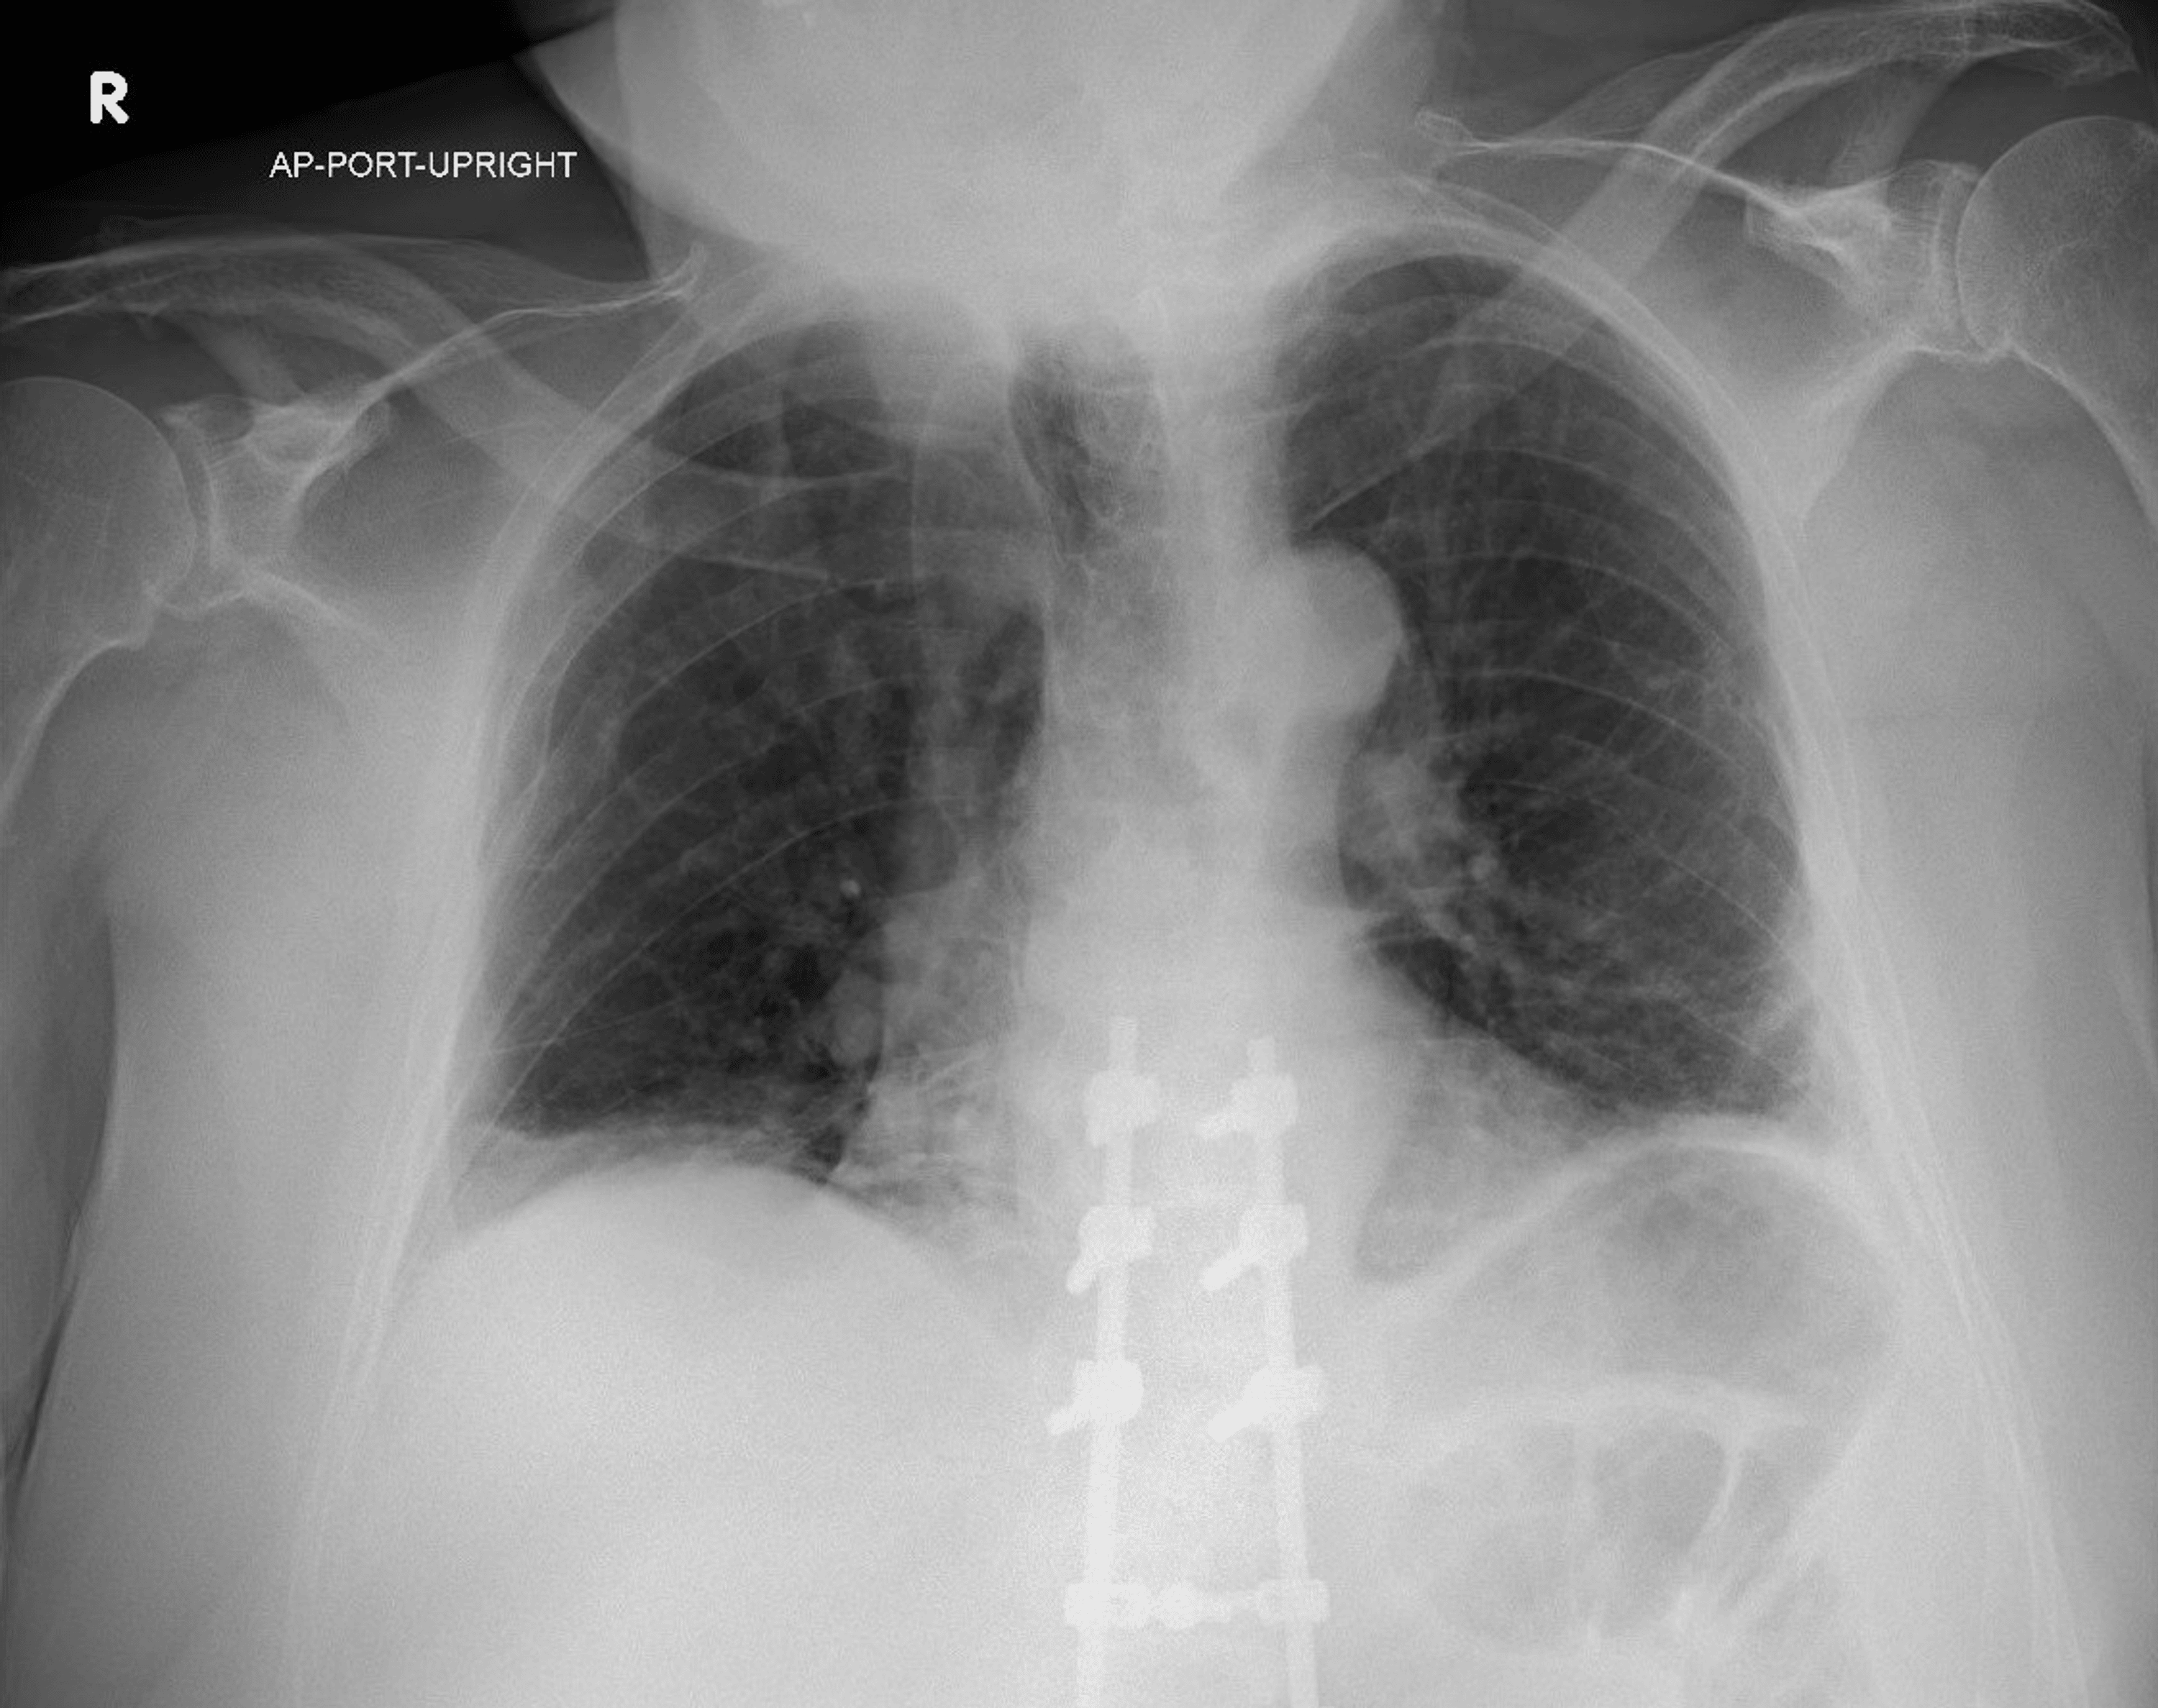

From henryoshoremoh.blogspot.com

RADIOLOGY, PREGNANCY, INFECTION AND TREATMENT CHEST RADIOLOGY (5193 Is Cxr Safe In Pregnancy however, confusion about the safety of these modalities for pregnant and lactating women and their infants often results in. Exposure of an unborn baby to radiation may cause a slight increase in their risk from radiation. what are the effects on my baby? The higher the level of. In fact, the american college of obstetricians and. For example,. Is Cxr Safe In Pregnancy.